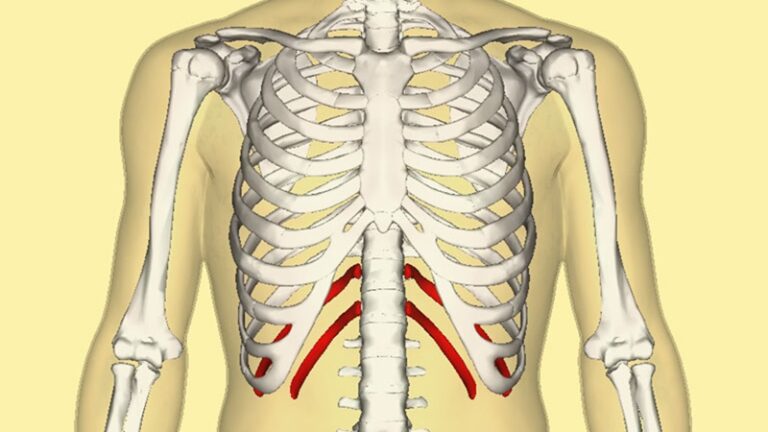

Xương sườn là một phần quan trọng trong cấu trúc cơ thể…